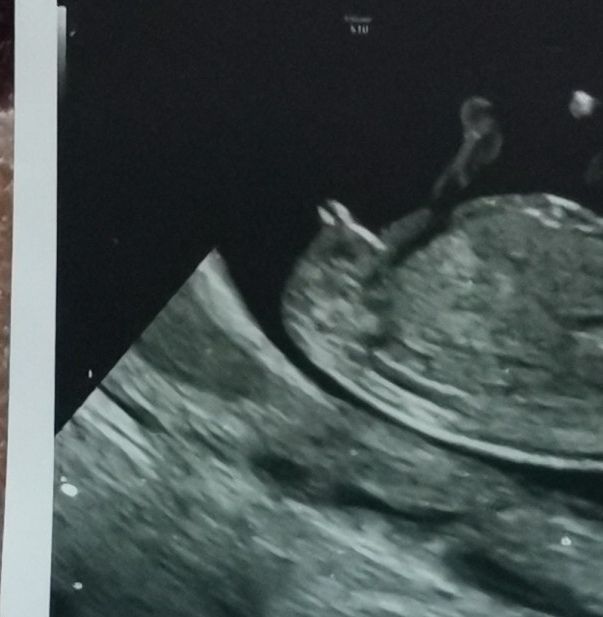

Мария, вот мой мальчик для сравнения. И тоже ничего мега вздёрнутого. Кровь подтвердила. Вам желаю здорового ребёнка!) Изображение

29.10.2023

Светик, спасибо большое, я здесь вообще ничего не понимаю, самое главное здоровый малыш